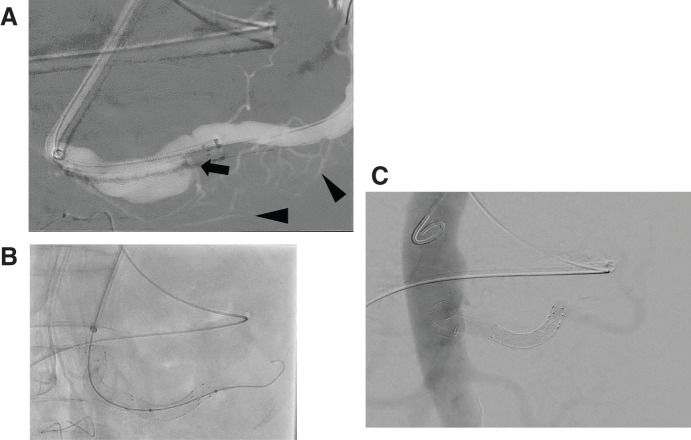

A 59-year-old patient was undergoing careful monitoring of an isolated superior mesenteric artery dissection discovered 6 years prior. He was admitted after outpatient imaging revealed multiple visceral aneurysms including common hepatic and splenic artery aneurysms that had enlarged. Based on anatomical reasons and the past history, the splenic artery aneurysm was treated with endovascular therapy, while the common hepatic artery aneurysm was resected, and blood flow reconstruction was performed. The patient was discharged without any complications. Visceral artery aneurysms have diverse locations and morphologies, illustrating the importance of treatment strategies that consider the blood flow to the organs.